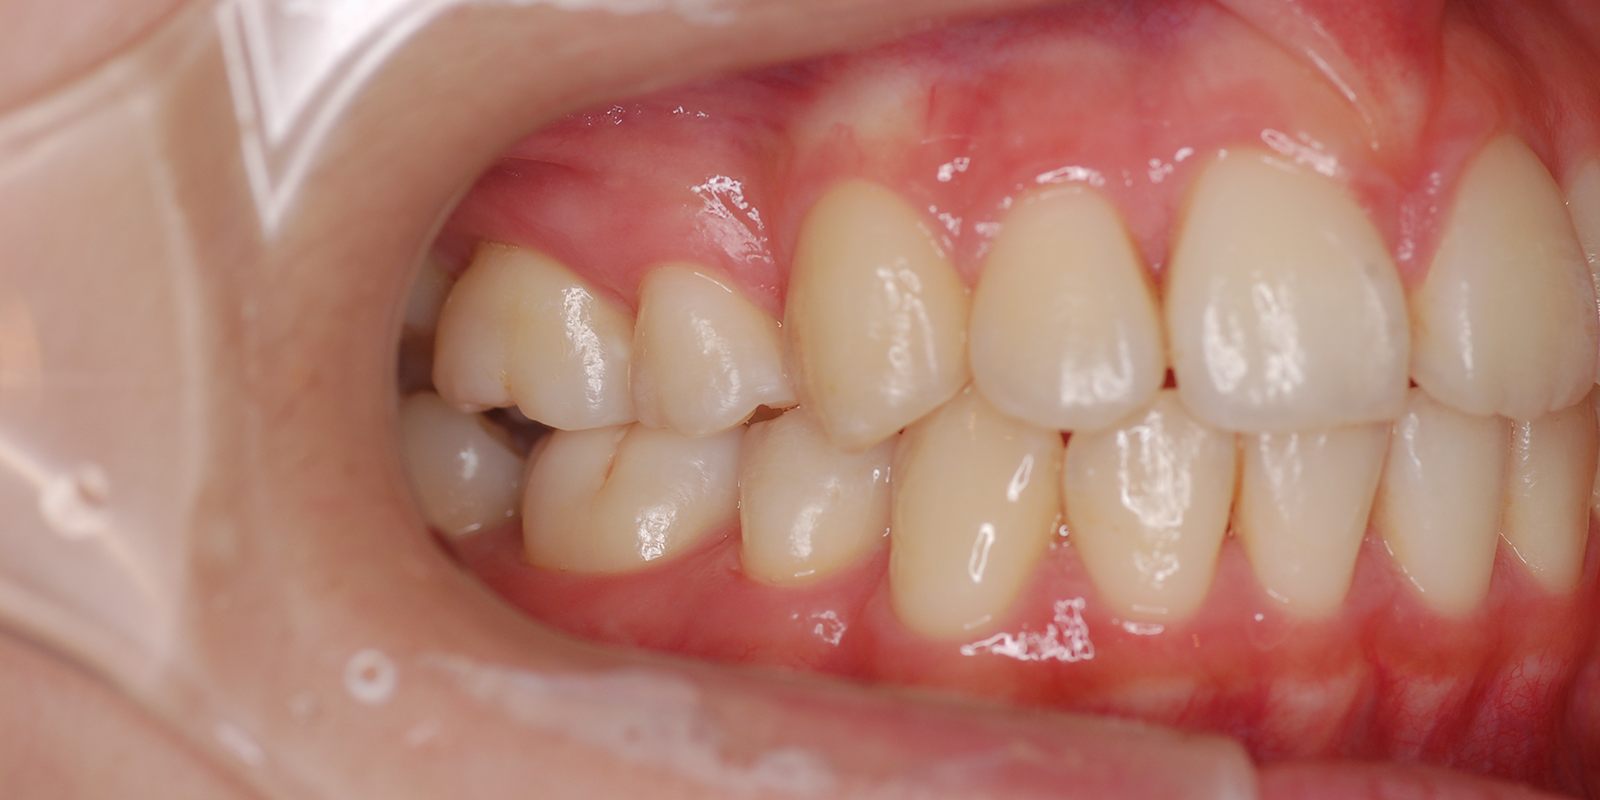

術後

| 主訴 | 受け口 |

| 診断 | アングルⅢ級反対咬合 |

| 初診時年齢 | 8歳1か月 |

| 装置 | 舌側弧線装置 |

| 抜歯・非抜歯 | 非抜歯 |

| 治療期間 | 2年7か月 |

| 通院回数 | 20回 |

| 治療費 | 25万円 矯正歯科治療は公的医療保険の適用外の自費(自由)診療となります |

| 治療のリスク | ・ばねが口から飛び出してくることがあります ・装着当初話しにくい場合があります |